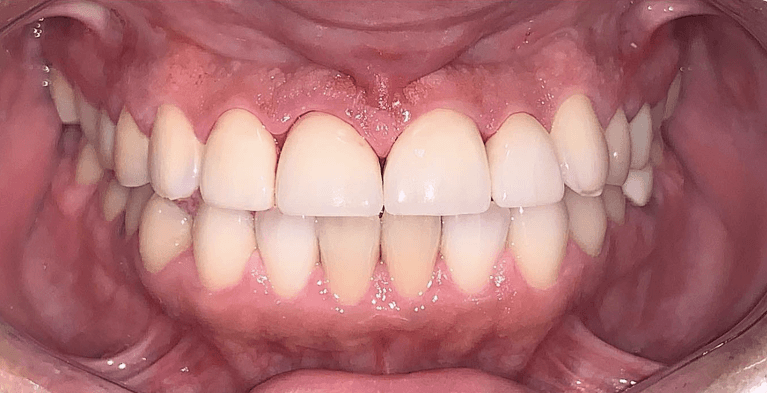

Before and after with Invisalign orthodontic treatment. Pictures taken with different phones at different setting. Used total of 27 aligners/trays. Treatment time 13.5 months